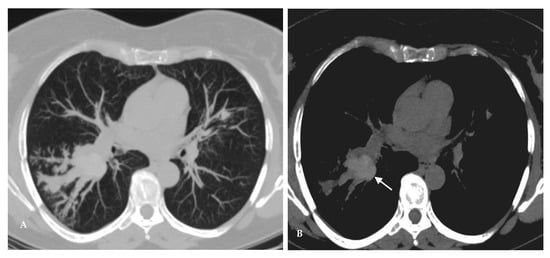

2.1. Lung Nodule or Mass

2.3. Chronic Cavitating Disease